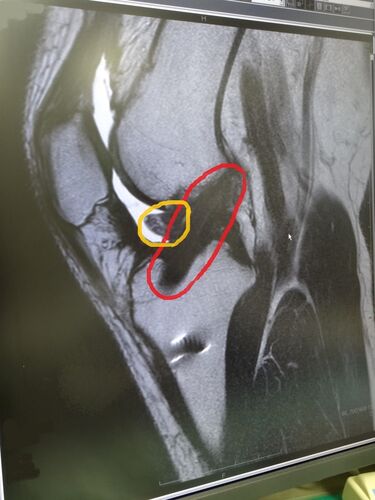

赤い斜めな黒いのが再建された前十字靭帯。 黄色いのが余計に成長した靭帯(過成長)で伸ばすのに邪魔してるかも?とのこと。 素人目?に「しっかりした靭帯出来てんじゃね?」と勝手に思ってみたり。 それから財布の修理&長財布の発注。 瑞雲寺の小早川秀秋公…